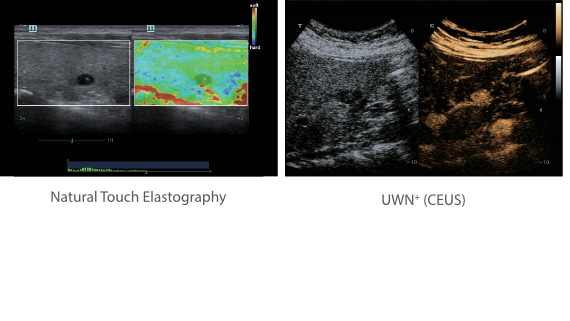

X-Insight ??? ??? ??? ??? ?? ??? ?? ?? ??????.

?????? ??? ???? ?? ???? ??? ??? ??? ???? ??? ??? ??? ?? ??? ???? ?????. ??? ?? ????? ???? ???? ??? ?? ??? ???? ?? ???? ??? ???? ???? ????.

???? ?? ??? ?????, X-Insight???? ??? DC-60 Exp ?? ??? ???? ???? ?? ??? ?? ??? ?? ???? ?????.

X-Insight??? ??? DC-60 Exp? ??? ??? ?? ?? ???? ???? ???(eXpress) ???, ???(eExceptional) ?????, ???? (eXceeding) ?? ??? ?? ????, ??? ???? ??? ??? ?? ???? ?????.